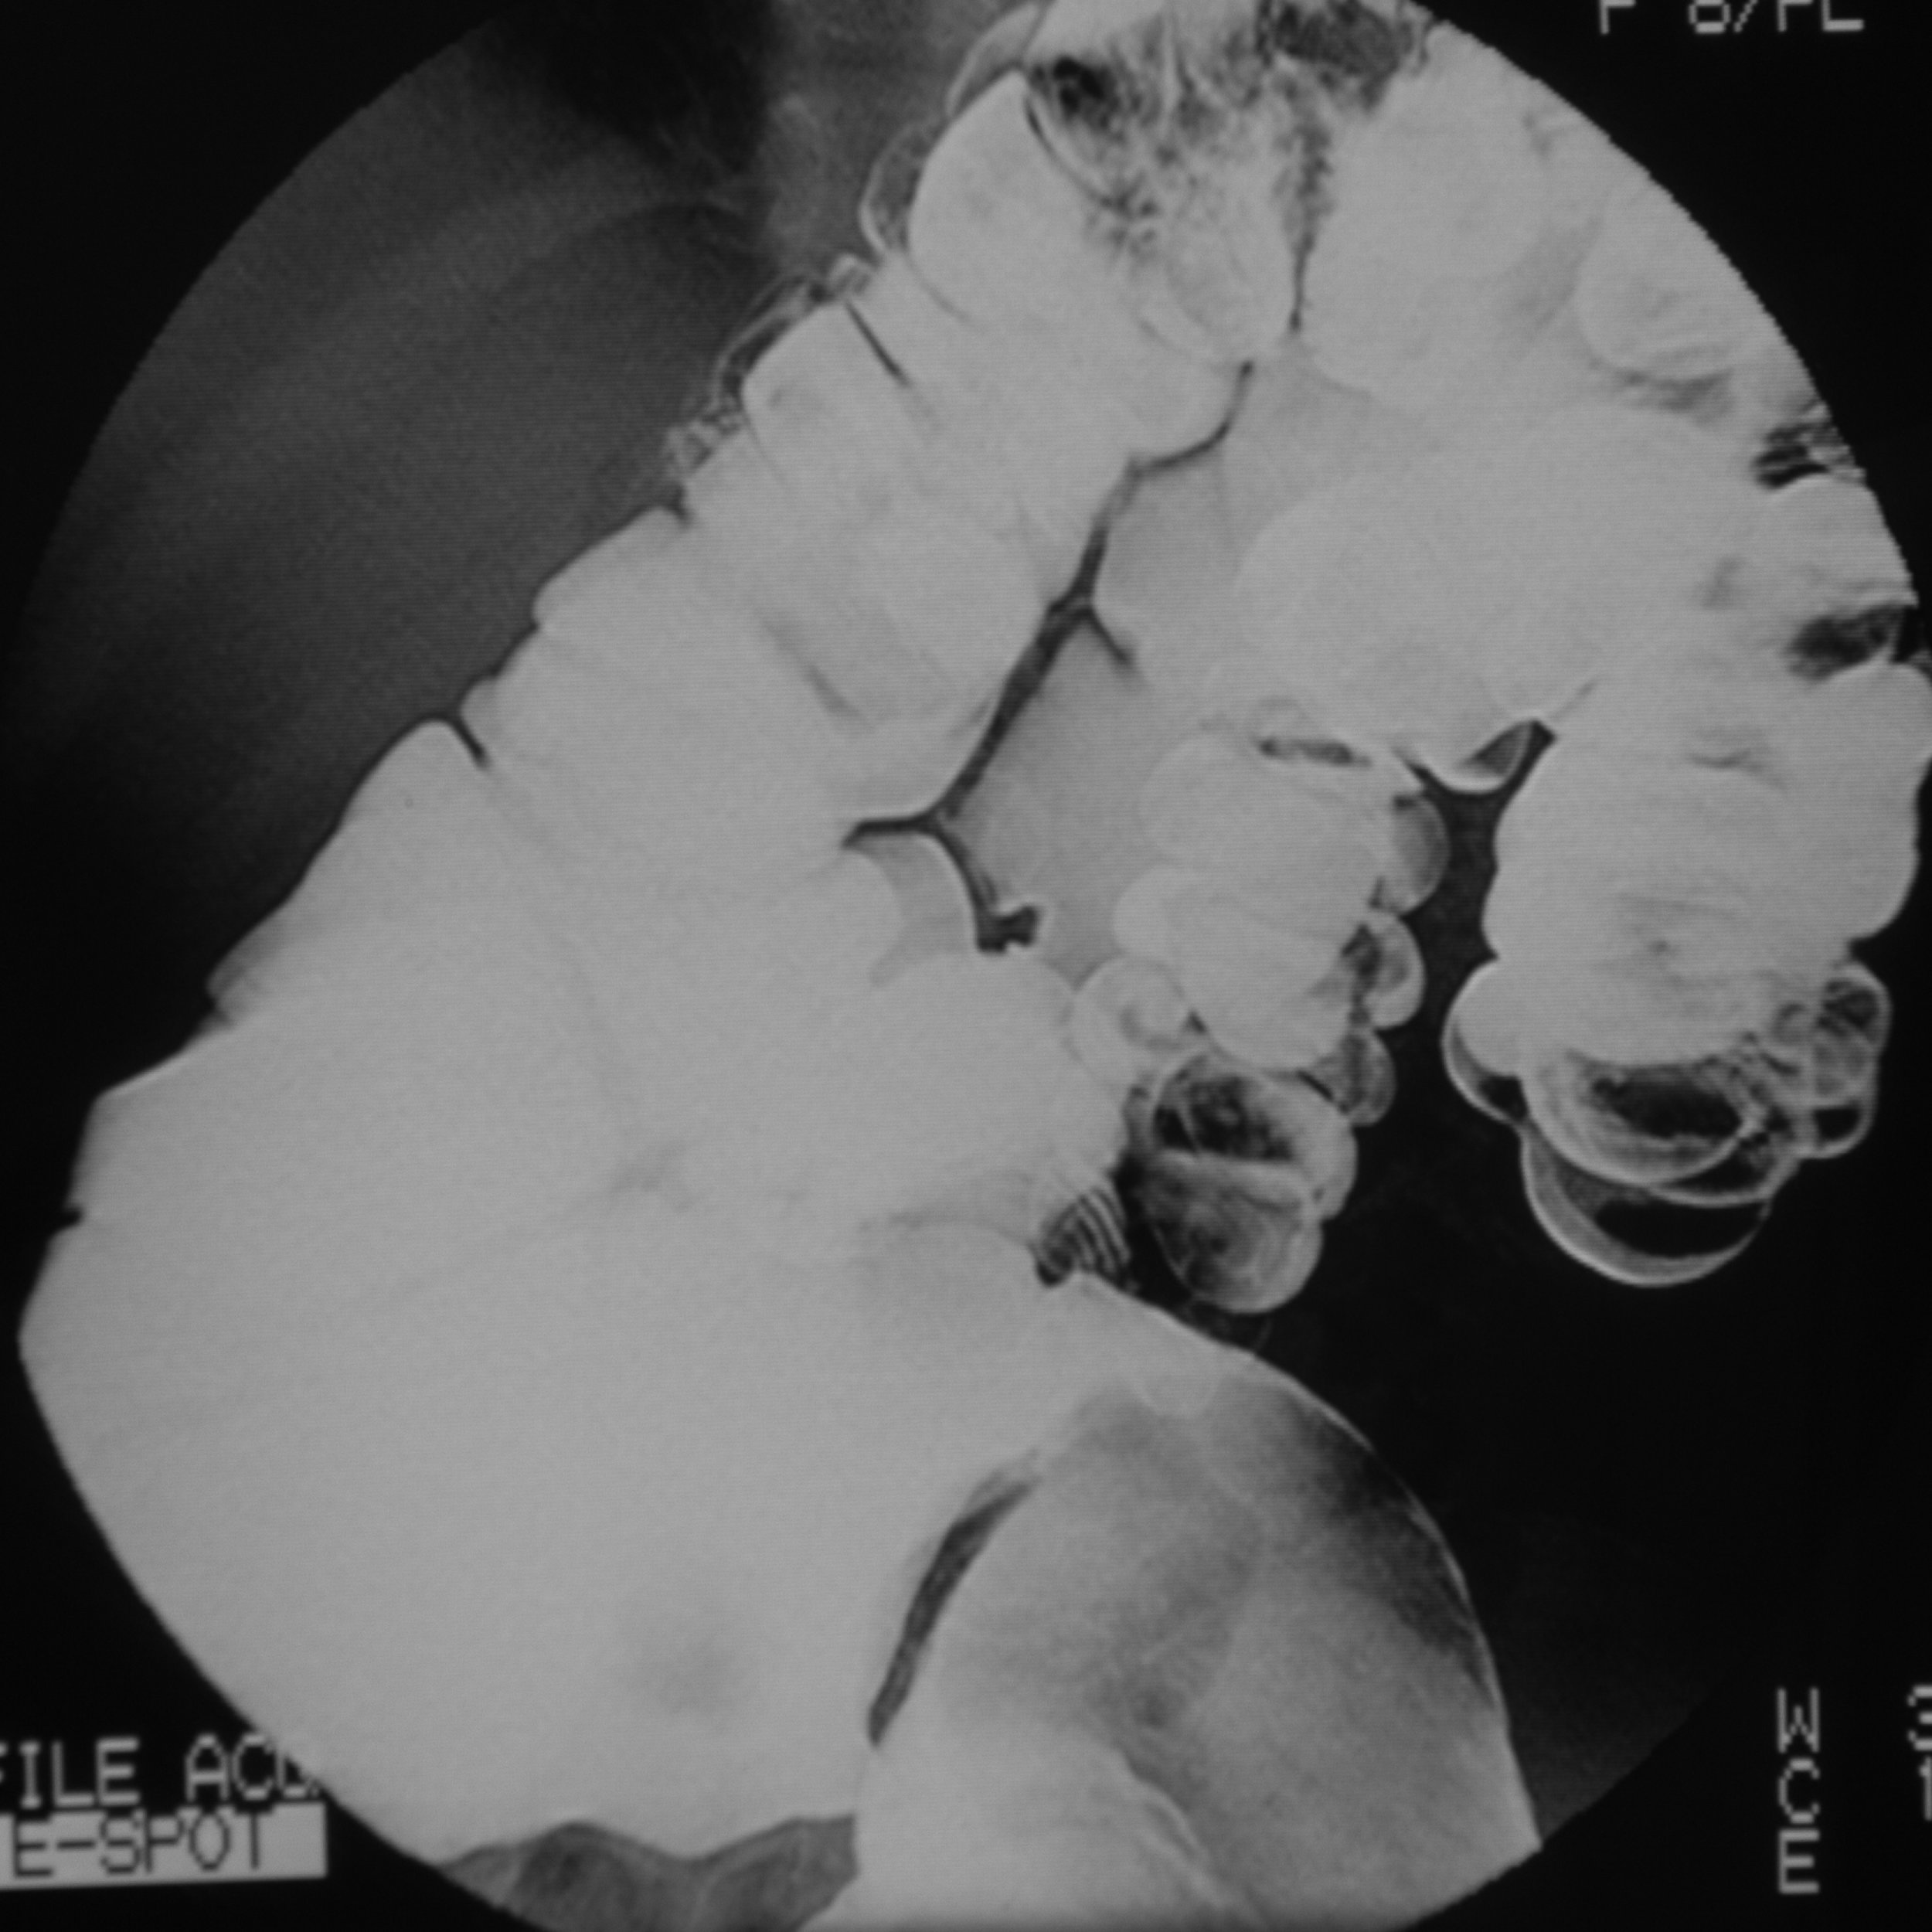

La principal ventaja

de la Radiología Digital, para el paciente, es la menor exposición a la radiación, ya que los equipos digitales procesan la imagen mediante un programa computacional que permite mejorar y corregir algunos defectos que pudiesen haber. Esto permite que las Radiografías Digitales tengan un porcentaje menor de repetición.

La imagen que entrega una Radiografía Digital es de mejor calidad en comparación a una radiografía convencional. Asimismo, las Radiografías Digitales generan un registro digital que puede ser utilizado para reimprimir la imagen en caso de ser necesario, mientras que en un equipo convencional sería necesario repetir la toma radiográfica en caso del extravío de la placa.